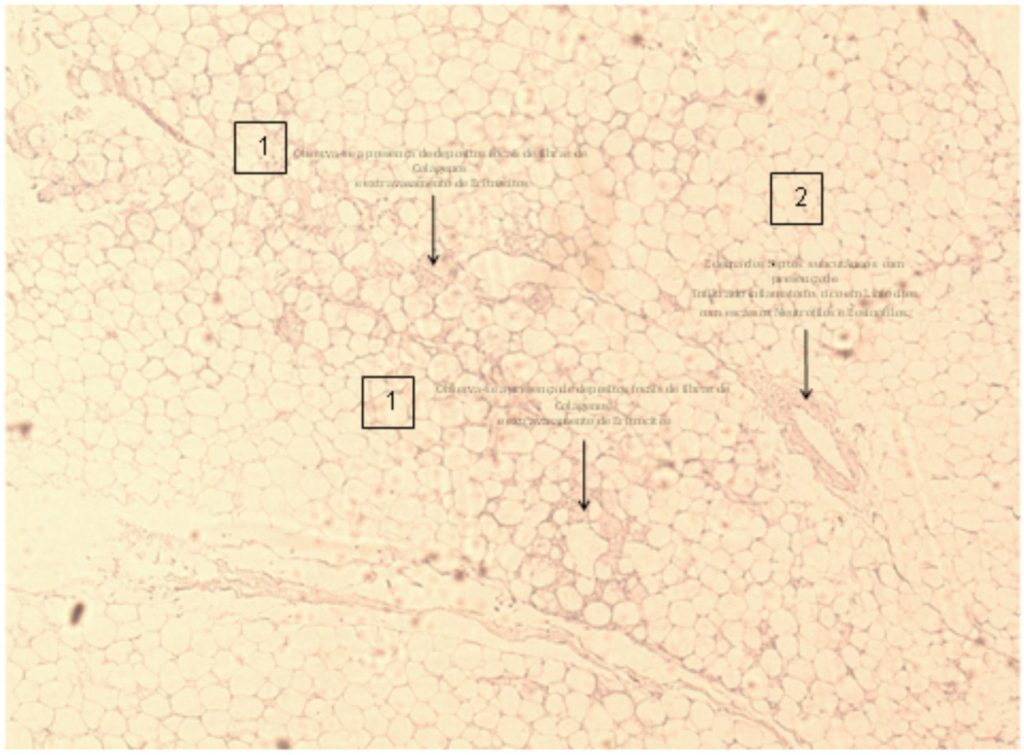

Figura 5

Depósitos focais de colágeno e extravasamento de eritrócitos (1). Edema de septo subcutâneo com infiltrado inflamatório (2)